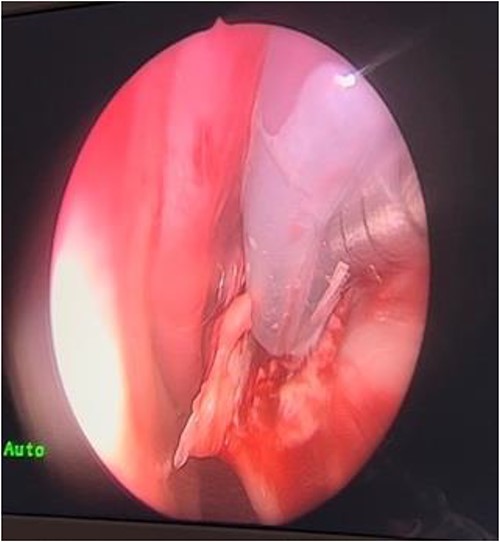

In the operating room (OR), examination under general anesthesia (GA) using a rigid nasal endoscope showed a heterogenous mass in the posterior nasal septum destructing the vomer, rostrum, and sphenoid wing. The mass was evacuated by the EEA while using the navigation system. The evacuation extended posteriorly to the sphenoid sinus, laterally to the sphenoid wing, and superiorly to the skull base (Figs 3 and 4). Lastly, Doyle nasal splints were inserted bilaterally to prevent re-accumulation of a hematoma (Fig. 5). Post-operatively, NovoSeven was administered for optimization. The patient was discharged in stable condition, and 10 days later underwent removal of the splints in the OR under GA. He followed up post-operatively at the otolaryngology clinic and was doing well, with no further complaints of epistaxis.